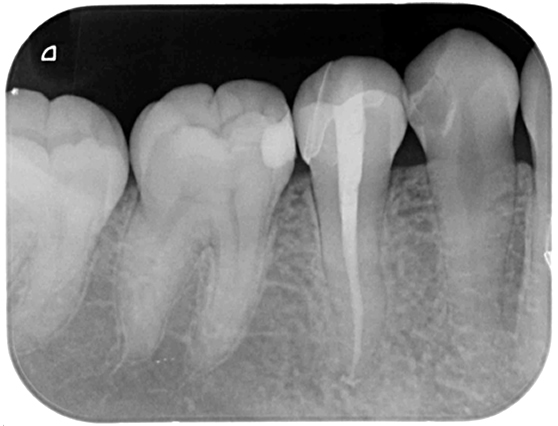

根管治療 症例 3

詳しく見る